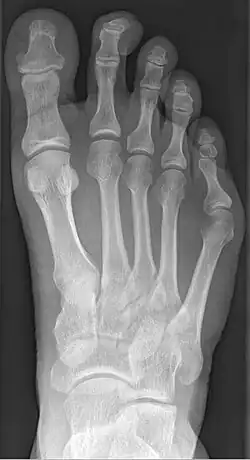

La bunionette est facilement diagnostiquée, car la saillie est apparente. Des radiographies peuvent être prescrites afin d'aider le chirurgien à déterminer l'ampleur de la déformation.